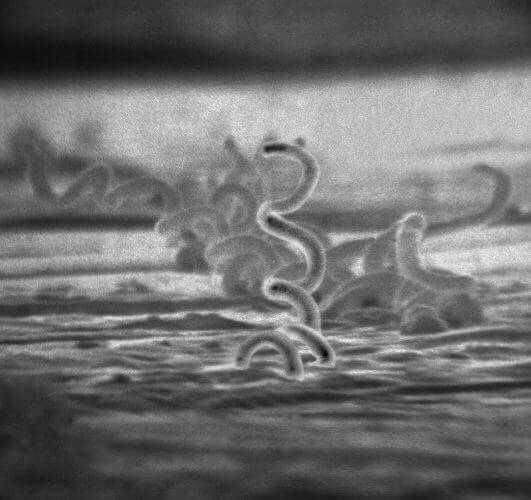

梅毒螺旋體的電子顯微照片。(圖取自維基共享資源,版權屬公有領域)